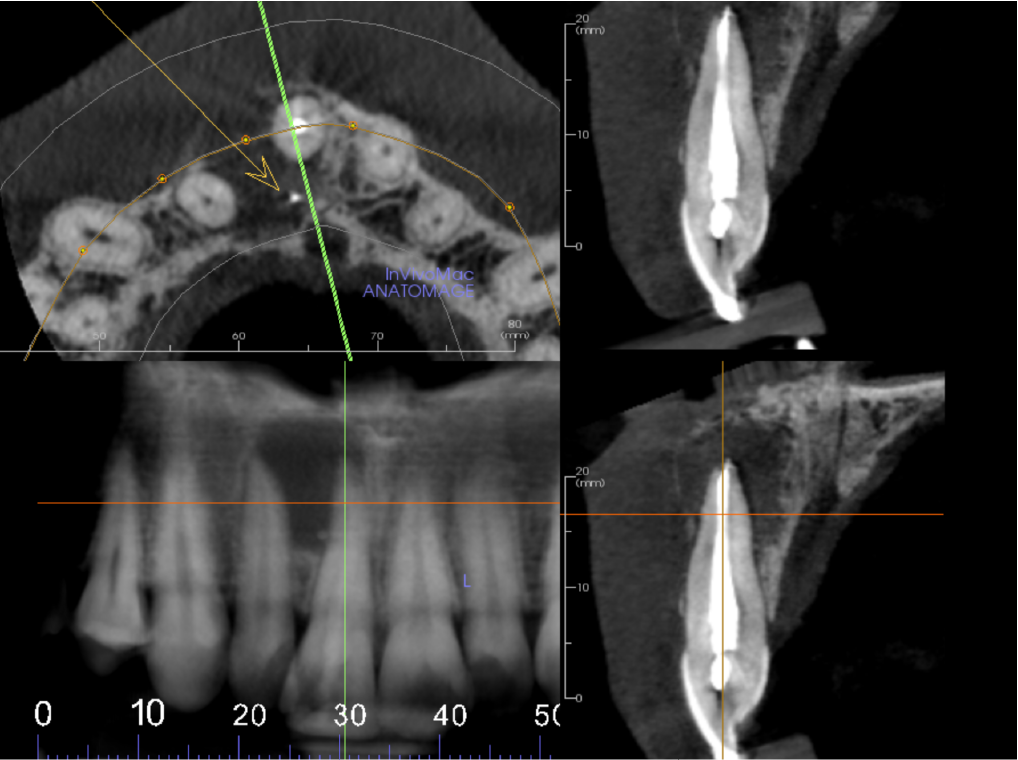

The UR1 is root filled with a small amount of extruded filling material inside the lesion. There is a well-defined, unilocular radiolucency measuring 12mm, extending from the UR1 apical region to the UR2 apex. The origin is probably from the apex of the UL1. The buccal cortex is expanded and perforated. The palatal cortex is eroded at the level of the oral opening of the nasopalatine canal. The lesion has not eroded the nasopalatine canal more superiorly. The appearance is that of a radicular cyst.

Axial view showing well defined unilocular radiolucency in UR1-UR2 area. The buccal cortex is expanded and perforated (arrow)

Axial view showing the palatal cortex eroded at the level of the oral entrance to the nasopalatine canal (arrow)

Cropped panoramic, axial and cross section of alveolar ridge UR1 region. UR1 is root filled to the apex with a small amount of extruded filling material inside the lesion (arrow)